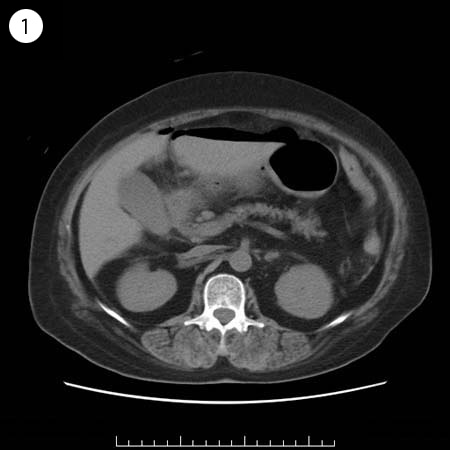

57歳 女性

単純CT